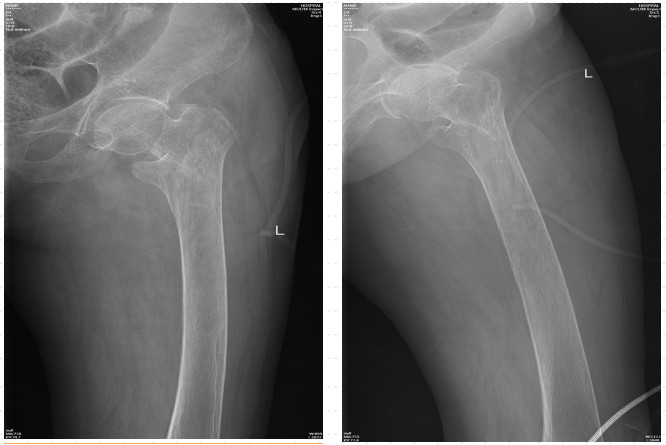

近日,88歲高齡的陳奶奶因滑倒摔傷,臀部著地,當(dāng)即感到左髖部疼痛,無法站立行走,活動明顯受限。陳奶奶的家人發(fā)現(xiàn)后立即將她送至我院急診科進(jìn)行救治。拍片后提示為左股骨粗隆間骨折,需要手術(shù)治療。

不幸的是,這次受傷造成了左股骨粗隆間骨折,陳奶奶將迎來第二次的髖關(guān)節(jié)手術(shù)!此次手術(shù)的風(fēng)險比上一次更高,術(shù)后治療與康復(fù)也更具有挑戰(zhàn)性!

術(shù)前